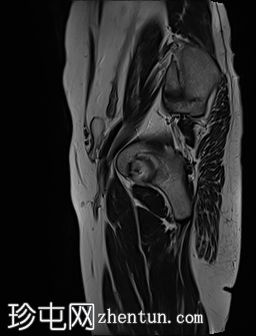

MRI

左侧阴囊空虚。

左侧睾丸位于盆腔左侧前壁,腹股沟管上方。其体积较小(与对侧正常的右侧睾丸相比)。T2加权像呈高信号,T1加权像呈低信号,未见明显局灶

性病

变。

右侧睾丸位于右侧阴囊内,大小和形状正常。

病例讨论

患者已知患有隐睾。评估睾丸大小以判断是否存在萎缩(本例已证实)以及是否存在任何睾丸局灶性病变非常重要。隐睾患者发生恶性

肿瘤

的风险较高。本例未见睾丸肿块。